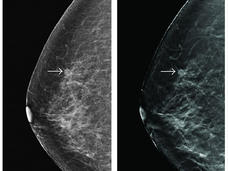

TMIST Trial Aims to Provide Clarity on Breast Cancer Screening Approaches

A large nationwide clinical trial called TMIST has been launched to compare two techniques used for mammograms: tomosynthesis, often called 3D mammography, and standard 2D digital mammography.